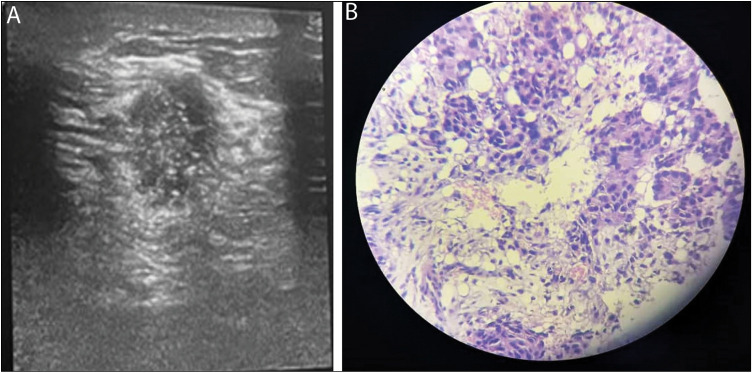

Background: Following recommended guidelines, palpable breast lumps in young women should be subjected to clinical-radiologic evaluation and tissue diagnosis where necessary. However, in our local practice, most benign breast lumps are also subjected to excision biopsy. Ultrasonography is the modality of choice in the evaluation of palpable breast lumps in young women.

Materials and methods: This was a prospective cross-sectional study of 87 adult females who had breast US and biopsy for palpable breast lumps in a tertiary healthcare center over a period of 10 months (July 2020-May 2021).

Results: The age range of the women was 18-39 years (mean 27.9 ± 7.09 years).Benign lesions were noted in 86.2% of patients. No malignancy was detected in women < 25 years. Ultrasonography had sensitivity, specificity, positive predictive value, negative predictive value, and accuracy of 100%, 93.4%, 70.6%, 100%, and 94.3%, respectively, in differentiating benign from malignant breast lumps following tissue diagnosis.

Conclusion: Ultrasonography and tissue biopsy are vital in the evaluation of breast lumps in women less than 40 years of age. Most (86.2%) of the lumps were benign, and no malignancy was detected in women < 25 years. The high accuracy of ultrasonography in distinguishing benign from malignant lesions suggests the need for conservative management of benign lumps in young women.